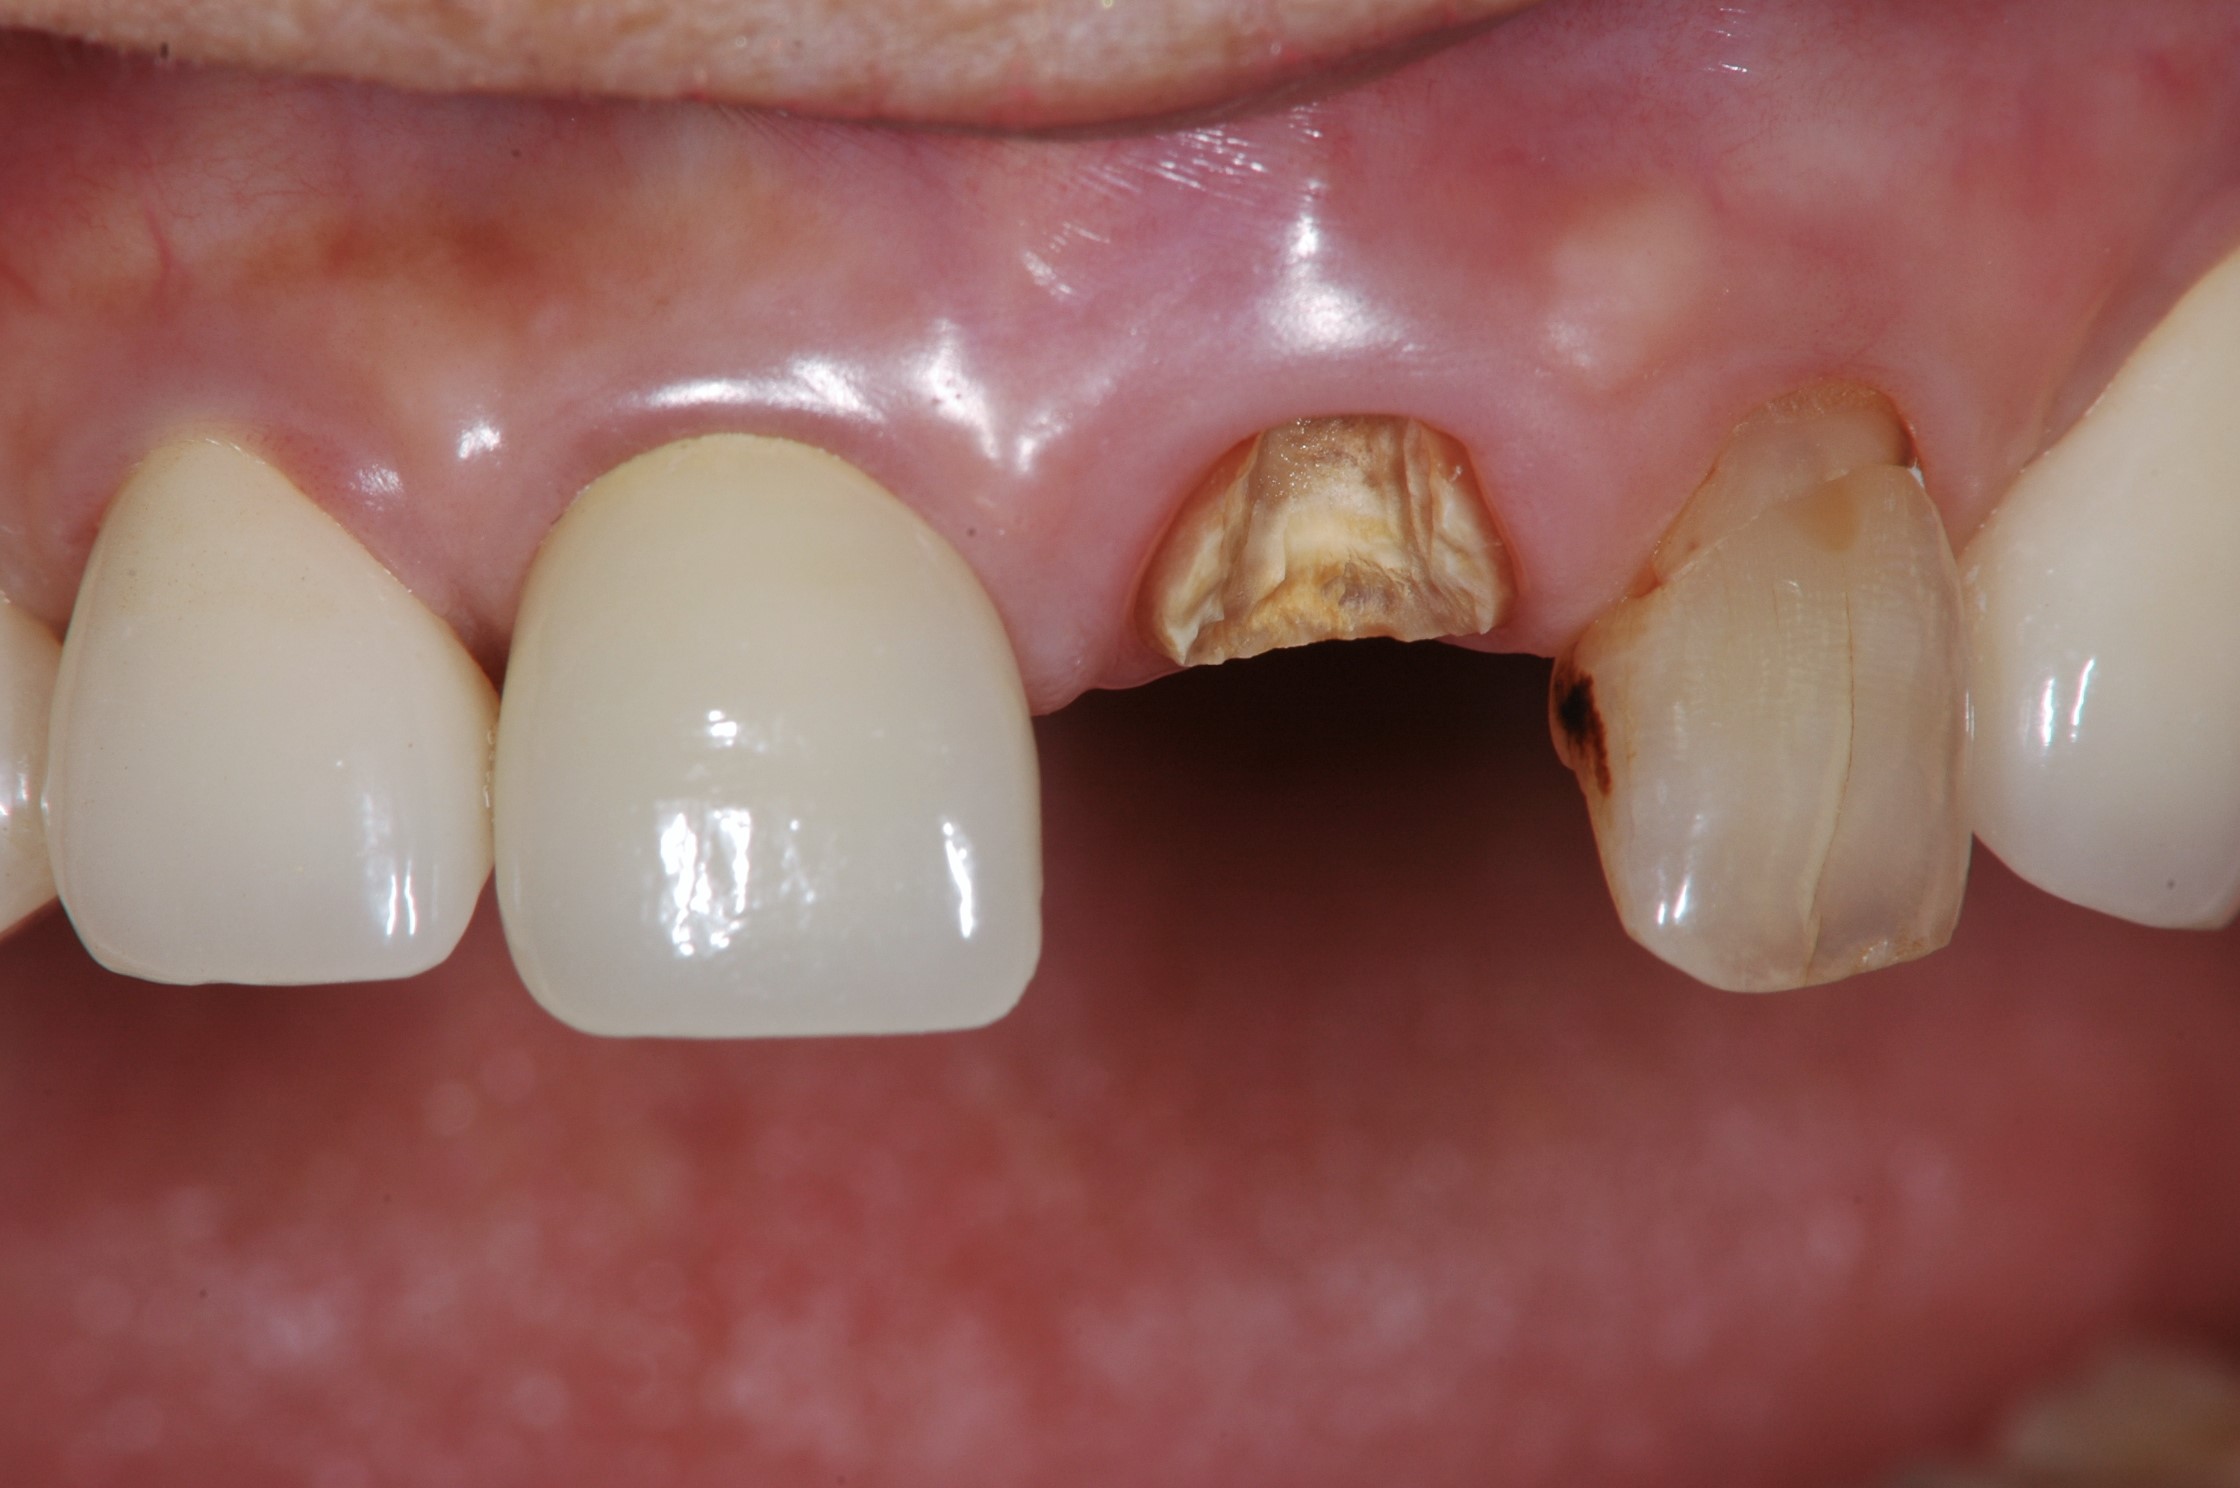

上顎欠損 抜歯即時埋入

初診時

インプラント埋入後最終補綴物